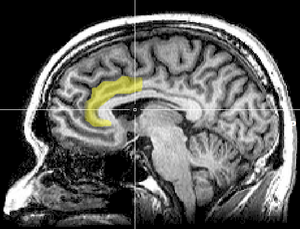

In light of individual brain regions often contributing to multiple emotions, a one-to-one mapping approach for hedonic pleasure or life satisfaction gives way to a more complex, network-based model of emotion.[16] As Kringelbach and Berridge (2009, p. 482) write, “analogous to scattered islands that form a single archipelago, hedonic hotspots are anatomically distributed but interact to form a functional integrated circuit.” [11] In rhesus monkeys, for instance, the rostral cingulate gyrus has been found to project to rostral superior temporal gyrus, midorbitofrontal cortex, and lateral prefrontal cortex and ventral anterior cingulate sends projections to the anterior insula cortex, premotor cortex, and orbitofrontal cortex, among others (most of which are implicated in pleasure or happiness, as discussed below).[17] Corticial and sub-cortical networks involved in pleasure and happiness have anatomical links to many regions, for instance, across the orbitofrontal, medial prefrontal, and cingulate cortices. While a consistent and discrete network of happiness per se has not yet been full delineated, we will now review the main candidates for such a network that have been most implicated in neuroimaging studies of happiness.

Basal Ganglia

The principal components of the basal ganglia include the nucleus accumbens (NAcc), striatum (caudate nucleus and putamen), substantia nigra and subthalamic nucleus.[19] Within these structures, a mini-limbic dopaminergic system including the nucleuss accumbens, ventral palladum and ventral tagmental area (VTA) is purportedly involved in the experience of pleasant emotion. Indeed, in one major meta-analysis,[15] almost 70% of happiness induction studies reported activation in the basal ganglia, across responses to happy faces,[20] pleasant pictures,[21] pleasant sexual and successful competitive arousal.[22] In Wager et al. (2003), positive emotions were found to be more likely to activate the basal ganglia than negative emotions.[23] The NAcc in particular appears to play a important role in happiness. One study found that as NAcc activation increased when viewing faces, happiness tended to increased possible driven by the NAcc’s enhanced dopaminergic activity.[24] Further, whereas anticipation of increasing rewards elicited both increasing self-reported happiness and NAcc activation, anticipation of increasing punishment elicited neither.[25]

The ventral pallidum also appears to be a key component to any happiness neural network. Of all the hedonic brain regions, only damage to the ventral pallidum fully abolished the capacity for pleasure in rodent studies[2] In humans, a case study also found anhedonia following bilateral lesion to the ventral pallidum.[28] However, while the NAcc, ventral palladum and other limbic components of the basal ganglia appear to be consistently implicated in reward circuitry, a one-to-one matching of the basal ganglia to happiness may be oversimplified. For one, while basal ganglia activation was reported in 70% of happiness studies (as mentioned above), it was also reported in 60% of studies evoking disgust.[15] In Murphy et al. (2003), similarly, a reliable and specific association existed between disgust and the basal ganglia[8]. However, it appears that the globus pallidus is the primary component of the basal ganglia implicated in disgust (in over 70% of the studies), leaving the NAcc, VTA, substantia nigra, and ventral pallidum exclusive in their involvement in pleasure and happiness.[8]

Orbitofrontal Cortex

Neuroanatomically connected to the nucleus accumbens is the orbitofrontal cortex (OFC), another brain region highly involved in the processing of pleasure and thus a strong candidate for any hedonic brain network. The OFC may further be split into a mid-anterior and more anterior region. The mid-anterior region is purported to be highly involved in the coding of the subjective experience of pleasure - neuroimaging studies have shown strong correlations to pleasantness ratings for food, sexual orgasms, drugs, chocolate, and music.[2] The more anterior region is supposedly involved in more complex positive reinforcers such as monetary gain.[2] A meta-analysis by Kringelbach and Rolls (2004) of 87 publications from 1994 to 2003 confirmed the involvement of different sub-regions of the OFC in both reward punishment. Whereas the lateral OFC is related to the evaluation of punishment, the medial OFC was found to be consistently involved in the processing of reward. [26]

Anterior Cingulate Cortex

The ventral part of the anterior cingulate cortex (ACC), or Brodmann area 24, is also connected to the nucleus accumbens (and many other regions implicated in emotion) and appears highly important for any neural network associated with happiness. Indeed, studies on therapeutic interventions involving either cognitive behavioral therapy or deep brain stimulation both found that reduced depressive symptoms were associated with increased activity in ventral ACC, along with increased hippocampus volume and a number of other metabolic changes.[27] Meta-analyses also implicate parts of the ACC in happiness. Murphy et al. (2003) for instance found that the rostral supracallosal ACC (as well as dorsomedial PFC) was the most consistently activated region found in happiness. But the same study found that the rostral part of the ACC was also activated by sadness.[8] In contrast, a more recent meta-analysis by Vytal and Hamann (2010) that included new data from additional 30 studies since Murphy et al. and used a more spatially sensitive activation likelihood estimation (ALE) method found that activation of both left ventral and rostral ACC were highly associated with happiness but not sadness, nor any other negative emotions.[5]

Based on recent meta-analyses in affective neuroscience, it appears that pleasure may be objectively measured through a combination of "hedonic" interconnected cortical and sub-cortical regions, including, but not limited to, dopaminergic components of the basal ganglia (NAcc, VTA, ventral palladum), the midanterior subregion of the orbitofrontal cortex, the right rostral and ventral anterior cingulate cortex, and, possibly, the right superior temporal gyrus. However, a unified neuroanatomy of happiness remains elusive. Given the wide variance among the meta-analytic studies and lack of clear consistency and specificity, we cannot be terribly confident yet in our ability to both predict subjective well-being nor discriminate levels of happiness between subjects based on their neuroimaging feedback.